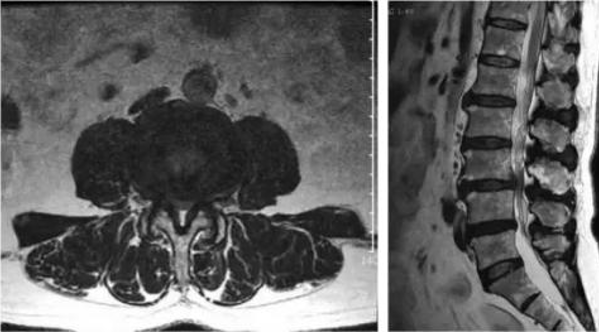

“第三板斧”,是腰椎核磁(MRI)檢查(如圖3)。腰椎核磁也可以從不同方向觀察骨質情況;更重要的是,對於腰椎間盤突出及周圍軟組織損傷等情況,MRI檢查比CT更具有優越性,因此更適合選擇。

因此,根據產生腰痛的大致原因可以分別做出選擇。如:受外傷後腰痛,嚴重者甚至需要專業人員護送至醫院就醫,這種情況,首選X線和CT檢查,首先檢視是否有骨折存在;若並有神經病態改變,則懷疑伴有脊髓損傷,要進一步行腰椎MRI檢視;若是非外傷所致腰痛的情況,多是因為生活中不良習慣所致,長期伏案學習工作,不正確的站姿坐姿,習慣性“北京癱”等都會造成腰痛,最常見的原因是腰椎間盤突出,首選是腰椎MRI,對於椎間盤觀察更有優勢。此外,還有部分年輕人,僅是腰肌勞損造成的筋膜炎性改變,也會產生腰部痛感,在MRI上顯示更好,也很適合選擇。